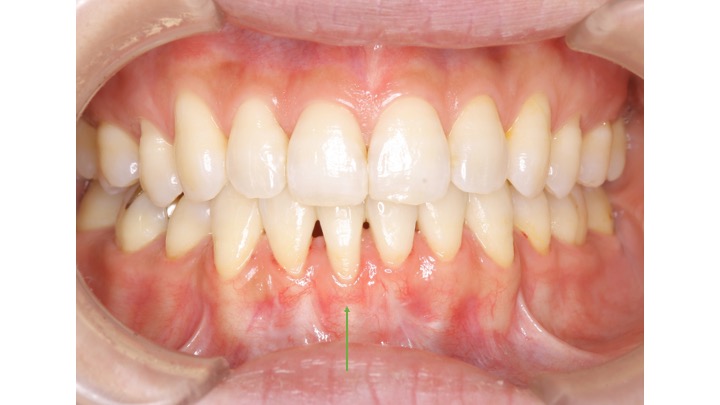

• 見た目の改善: 歯肉が下がることで、笑った時に歯が長く見えることがあります。根面被覆術により、自然な歯ぐきのラインを取り戻すことができ、見た目も向上します。